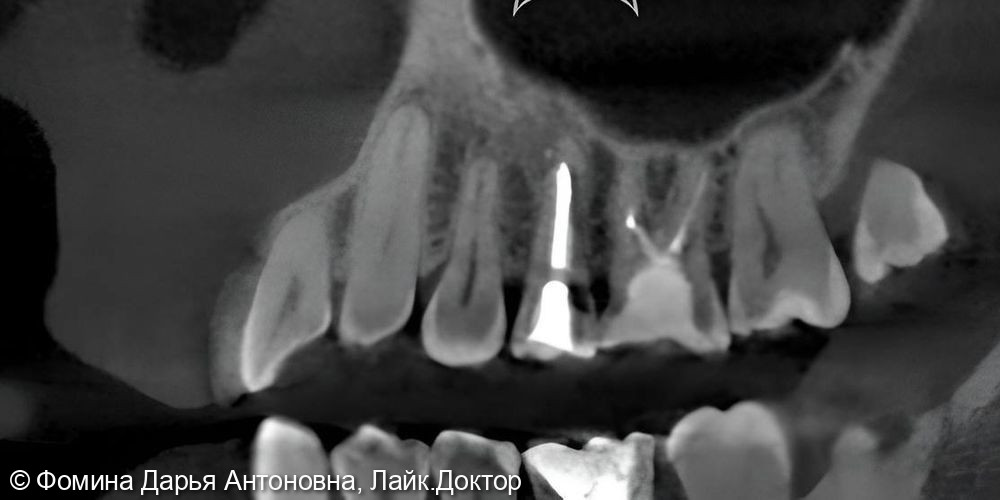

Зуб был пролечен около 5 лет назад в другой клинике и клинически не беспокоил. Однако при проведении КЛКТ выявили периапикальный очаг воспаления — скрытую инфекцию у верхушки корня.

Диагностика с помощью 3D-КТ: источник боли был обнаружен в 16 зубе – воспаление на верхушках корней. Зуб ранее лечили от кариеса более 5 лет назад.